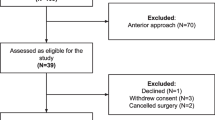

This retrospective study was approved by the institutional review board of our hospital. In our institution, a CT-based navigation system has been used to perform THA since October 2007. The older version of the navigation system was replaced with the newer version in January 2012. To investigate the accuracy of both navigation systems, subjects who underwent primary cementless THA with the same brand of prosthesis were selected according to the following criteria: (1) both cup and stem implantation were carried out under the guidance of the CT-based navigation system without any intraoperative failure of the navigation system; (2) the same brand of cementless acetabular cup (Trident PSL, Stryker Orthopaedics, Mahwah, NJ) and cementless femoral stem (Accolade TMZF, Stryker Orthopaedics, Mahwah, NJ) were implanted; and (3) there were no intraoperative or postoperative complications related to implant fixation, such as early implant migration or periprosthetic fracture. We selected the femoral stem to evaluate accuracy, because this stem was implanted with both versions of the navigation system and a sufficient period of time had elapsed to eliminate the influence of the initial learning curve for using the navigation system. 49 hips from 48 patients who underwent THA with the prostheses between July 2010 and December 2011 were included for the older version group. Consecutive 49 hips from 47 patients who underwent THA between January 2012 and June 2012 were included for the newer version group. All operations were performed by three surgeons: 1 senior surgeon (experienced surgeon) who was performing more than 100 THAs annually, and 2 resident surgeons (inexperienced surgeons) who were performing less than 30 THAs annually. Table 2 shows the demographic data and operator of both cohorts.